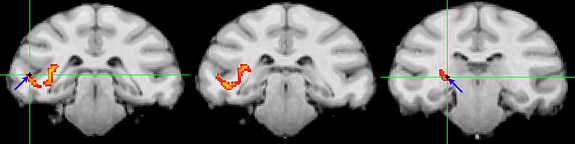

5772.06.01, 1200 Princeton study (EurekAlert): "A mysterious region [the pulvinar] deep in the human brain could be where we sort through the onslaught of stimuli from the outside world and focus on the information most important to our behavior and survival, Princeton University researchers have found. … the pulvinar regulates communication between clusters of brain cells as our brain focuses on the people and objects that need our attention. Like a switchboard operator, the pulvinar makes sure that separate areas of the visual cortex — which processes visual information — are communicating about the same external information"

| "After producing neural connection maps, the researchers used electrodes (blue arrows and green crosshairs) to monitor the direct communication paths (yellow-orange) between the pulvinar and clusters of brain cells, which in this case are in the temporal lobe. Image courtesy of Science/AAAS" |